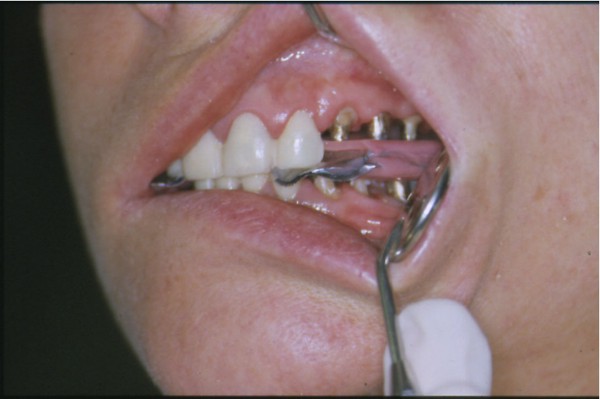

Entidades patológicas como el bruxismo, limitan la terapéutica odontológica y las certezas de un pronóstico favorable y prolongado en el tiempo. El strees, factor predisponente, y alteraciones morfológicas en la oclusión que impiden la disclusión de los sectores posteriores durante las excursiones de la dinámica mandibular, o factores desencadenantes. Caso Clínico Mujer , 53 años, derivado por especialista en Cirugía Máxilo Facial, con evidentes signos de hipertrofia de ambos maseteros. Clínicamente la carencia de las puntas caninas de ambos lados de ambas arcadas, nos habla de ciclos masticatorios eminentemente horizontales, tipo rumiante, donde el fenómeno de DOBLE DESGASTE de las cúspides estampadoras se pone en clara evidencia.(Fig.3 y 4 ) Ambos fenómenos(desgaste exagerado y extrusión dentaria nos habla de una invasión del espacio del maxilar superior, mediante la elevación del inferior, con las lógicas consecuencias musculares por acortamiento: Hipertrofia, acúmulo de ácido láctico, sobrecarga de los elementos tendinosos y capsulares, etc. Se le hace saber al paciente acerca de la necesidad de múltiples técnicas de Rehabilitación ANTES de llegar a reponer sus piezas perdidas. Se le pone en conocimiento de la necesidad de reponer SOLO hasta su primer molar, el que se reemplazará mediante una PREMOLARIZACIÓN, dado que el ancho de su cresta no permite reemplazar un primer molar salvo con riesgos de invadir el ESPACIO BIOLÓGICO necesario para un buen desarrollo de sus funciones. Es necesario tener en cuenta, que la pérdida de dimensión vertical por excesivo desgaste de la porción coronaria es siempre acompañada, por un descenso de las estructuras corticales, desfavoreciendo la relación CORONO/RADICULAR, lo que hace fundamental el ejercicio de unas fuerzas oclusales VERTICALES, a fin de no aumentar la movilidad de las piezas, una vez que la altura adecuada haya sido restablecida, verticalidad que solo se alcanzará mediante la implementación de una GUÍA ANTERIOR adecuada. Se estudia el caso clínicamente y se toman modelos de estudio debidamente montados en articulador semi ajustable en posición de ORC que es la única posición posible para rehabilitar, sin incurrir en alteraciones posicionales de la ATM, ni de elongaciones musculares y tendinosas que generen una nueva situación de strees muscular y empujen al sistema al bruxismo. Se analizan los modelos en forma estática y dinámica, donde se observan no solo las facetas parafuncionales de desgaste sino también la carencia de disclusión canina, patología generadora de dichas facetas, y que, Se confecciona un Encerado de Diagnóstico(Fig.A/B) a partir del cual se tallan las piezas en los modelos y se reproduce un juego completo de provisionales a utilizar durante el procedimiento clínico. (fig. 9) Se realizan las endodoncias y se refuerzan con Pernos Muñones Colados en oro, mediante los conceptos de Alineación Tridimensional correspondientes, instalándose los provisionales efectuados a partir del encerado de diagnóstico, los que cumplen con la tarea de discluir los sectores posteriores , tal como se concibió en dicho encerado.(Fig.10-11-12-13-14) Transcurridos seis meses de control, donde se verifican las funciones del sistema, dentro de un marco adecuado de ortofunción en el cual tal vez el más importante índice es el escaso desgaste de los provisorios, los que funcionan en una adecuada OCLUSIÓN en RELACIÓN CÉNTRICA y DIMENSIÓN VERTICAL ,situación esta apoyada por la presencia nocturna de una férula de Relajación, donde podemos observar y además «escuchar» al enfermo decirnos de su mejoría masticatoria y de la desaparición del «estado de agarrotamiento» que sentía en la boca al despertar, verificando que se siguen produciendo las disclusiones adecuadas en todas las excursiones mandibulares. Realizamos entonces al estudio radiológico adecuado, procediendo a instalar ocho(8) implantes roscados, tres de los cuales son insertados con una ligera elevación de ambas mucosas sinusales intra alveolarmente.(Fig.15-16-17) Transcurridos tres meses más y verificando la correcta cicatrización tomamos impresiones para realizar los abuttments de oro correspondientes, sobre los que instalamos un nuevo juego de provisionales que ya dan carga a los implantes.(Fig.18-19-20-21-22) Ahora estamos en presencia de un Sistema Estomatognático que presenta las características idoneas para funcionar, características estas que observamos permanentemente sobre todo la función de la GUIA ANTERIOR. Recién entonces confeccionamos las Restauraciones Periféricas Totales, las que serán realizadas en Porcelana sobre Oro . Se procede entonces a la confección de los sectores posteriores constituidos en este caso por tres premolares en cada hemiarcada de cada maxilar.(Fig.29-30) Se constatan la Estética, el Ajuste Cavo Superficial, El Espacio Libre Interoclusal, la Dinámica Mandibular,etc.(31-32-33-34-35-36-37-38-39-40) Evidentemente un caso exitoso no muestra las bondades de un método. Sin embargo, la casuística popular acerca de la imposibilidad de ser implantados aquellos pacientes que padecen bruxismo es tan frecuente como realizar en bruxómanos, coronas totales con oclusal metálica a fin de no permitir que las fuerzas de la oclusión destruyan nuestro «trabajo, sin tener en cuenta que no es la dureza del metal quien evita la destrucción…. BIBLIOGRAFÍA: 1-Oclusión y Diagnóstico en Rehabilitación Oral. 2-Disfunción temporo Mandibular y Equilibración Oclusal. 3-Rehabilitacion Bucal. 4-Problemas Oclusales. 5-Oclusión. 6-Oclusión. Conceptos para el Clínico. 7-Disfunción temporo Mandibular. 8-Neurofisiología de la Oclusión. 9-Gnatología.Principios y Conceptos.José dos Santos. 10-Oclusión y Rehabilitación. 11-Procedimientos Clínicos y de Laboratorio de la Oclusión Orgánica.

A la inspección se observan claros signos de Bruxismo como también de pérdida de Dimensión Vertical y un moderado clicking en la ATM derecha, con pérdida de piezas dentarias del sector posterior y sensación de cansancio muscular a los lados de la cara sobre todo al despertar.

A la palpación no se verifican músculos con miositis y clínicamente la dinámica mandibular en apertura y cierre no muestra desviaciones.(Fig.1 y 2 )

Como así también las extrusiones producto de las exodoncias realizadas anteriormente. (Fig. 5 y 6 )

El relato del especialista a través de la enferma, confirma la indisposición para implantar debido a la exagerada disfunción muscular que hace presumir el fracaso de los implantes debido a dichas fuerzas y a las características horizontales de las mismas.